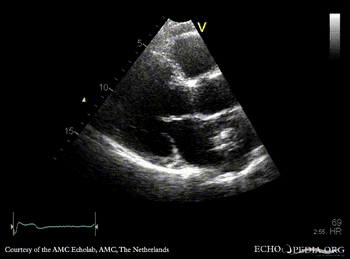

| Courtesy of: AMC Echolab, AMC, The Netherlands | |

| PLAX: dilated left ventricle, myxoma in left atrium | PLAX: dimensions of myxoma |